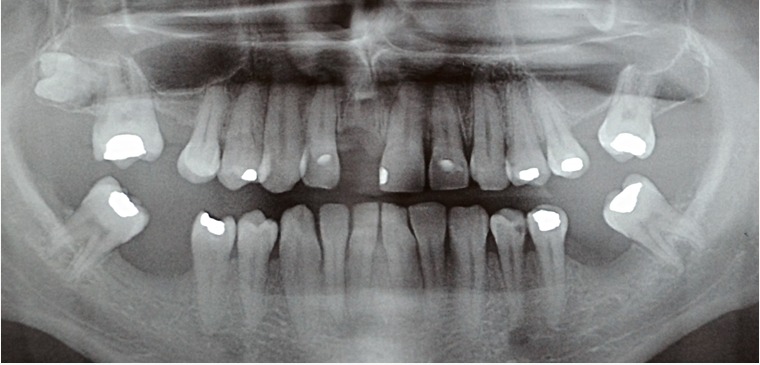

Região do elemento 11 edêntula. Foi realizado o planejamento para instalação de um implante na região desdentada, tentando deixar o mais parecido com o dente vizinho. Após exames complementares e planejamento, foi realizada a instalação de um implante Cone Morse 3.5×10 mm com enxerto Lumina Bone na região vestibular.